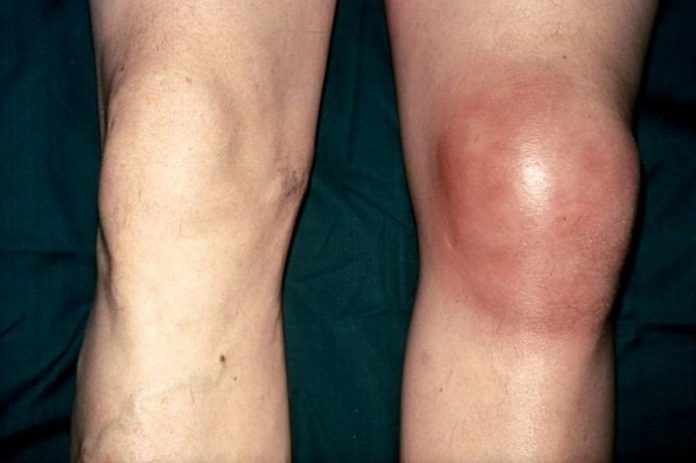

Заболевание также чаще всего диагностируется у мальчиков 10-14 лет. Хондропатия надколенника развивается в области крепления сухожилий к коленной чашечке, препятствуя поступлению питательных веществ из синовиальной жидкости к хрящевым тканям. Ведущие симптомы патологии — спонтанные боли, выраженность которых повышается при движении или при пальпации коленной чашечки. Если в полости сустава накапливается выпот, то кожа над ним разглаживается, краснеет, становится горячей на ощупь. Длительность течения этого вида хондропатии — несколько месяцев. Интенсивность болевого синдрома постепенно снижается, а затем происходит полное восстановление поврежденных структур.

- отечность, гиперемия из-за переполнения кровью сосудов, повышение местной температуры;

Подросток начинает заметно прихрамывать, старается не делать полный упор на стопу, чтобы минимизировать боль. Также возможно ослабление мышц с дальнейшей атрофией, укорочение ноги на несколько сантиметров. При накоплении экссудата в полости сустава и развитии воспалительного процесса происходит ухудшение самочувствия, вплоть до диспепсических расстройств. Изменяется психоэмоциональное состояние больного. Он становится вялым, апатичным, сонливым или, наоборот, раздражительным, вспыльчивым.